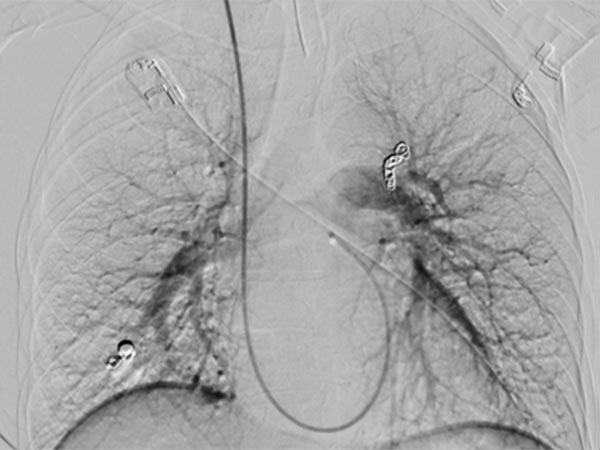

Die Abschluss-DSA über den Truncus pulmonalis zeigt keinen Zustrom mehr in die pulmonalen AVM.

Die Abschluss-DSA über den Truncus pulmonalis in der Parenchymphase bestätigt den vollständigen Verschluss der pulmonalen AVM.